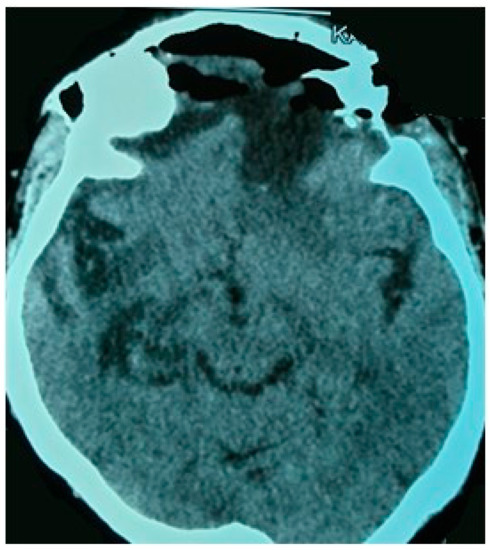

2.4.3. Preoperative Imaging

4.5. Neuroimaging Features and Differential Diagnosis